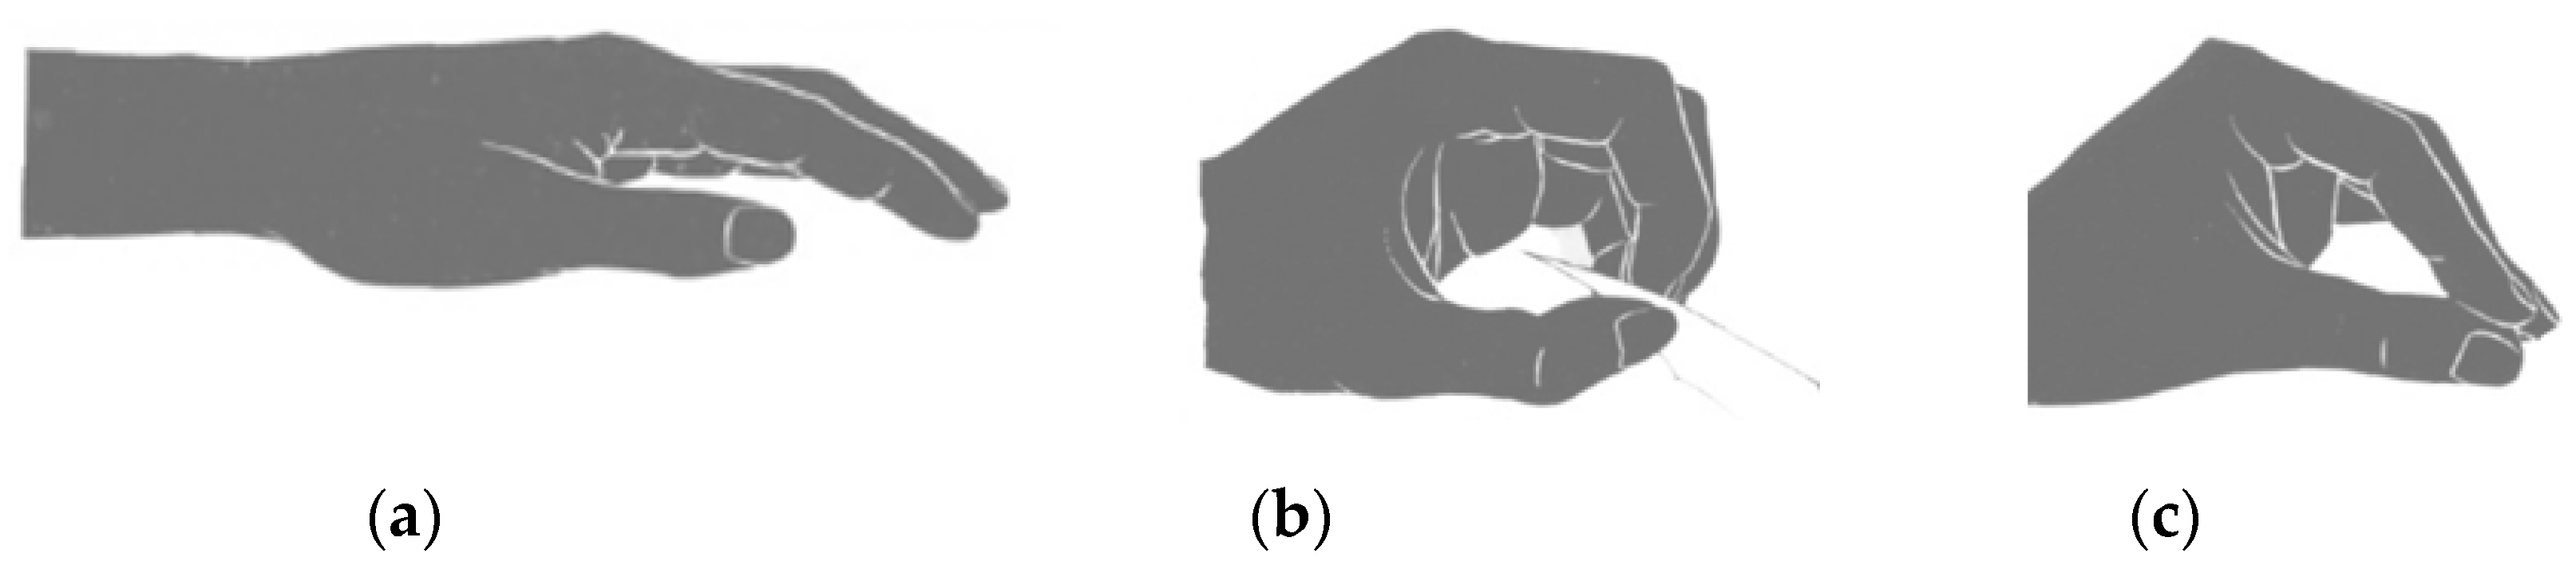

2.4. Parametric Assessment of Morphological Changes in Forearm Tissues When Performing Hand Actions Based on MRI

3.1. Study of Morphofunctional Activity of the Forearm Muscles When Performing Actions